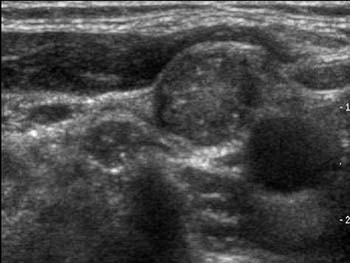

Papilläre und medulläre Karzinome metastasieren mitunter auch in die angrenzenden Lymphknoten, was im Ultraschall

oder auch im MR

zur Darstellung kommen kann. Papilläre und medulläre Karzinome können schon in jugendlichem Alter auftreten.